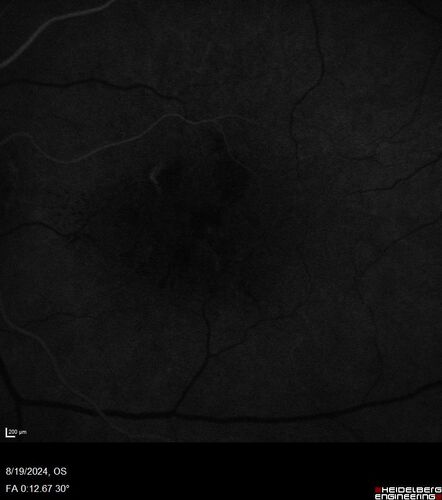

Wet AMD - Occult CNVM and Geographic atrophy

77 year old female with mild vision loss - 20/32 - responded to Avastin

Occult CNVM wet AMD and Geographic Atrophy